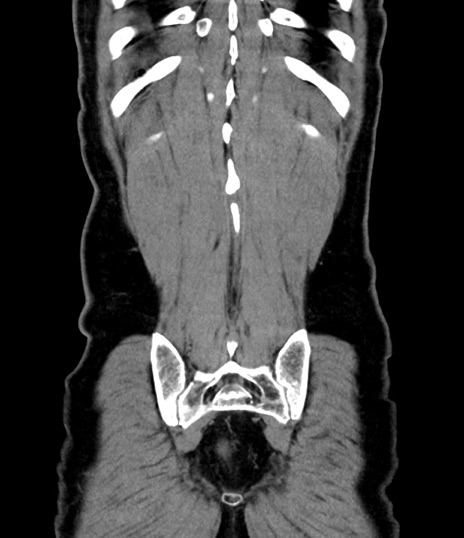

横断像

【症例】 60歳代男性

【主訴】 黒色吐物

【現病歴】 4日前から嘔気自覚、2日前の朝食後にも嘔気あり、自分で手で嘔吐反射起こし嘔吐したところ血が混ざっていたため受診。

【既往歴】 5年前汎発性腹膜炎を伴う急性虫垂炎で手術、高血圧、前立腺肥大症、高脂血症

【身体所見】 腹部正中に手術癩痕あり 腹部平坦・軟圧痛なし膨満感あり

【データ】WBC 8400、CRP 4.54